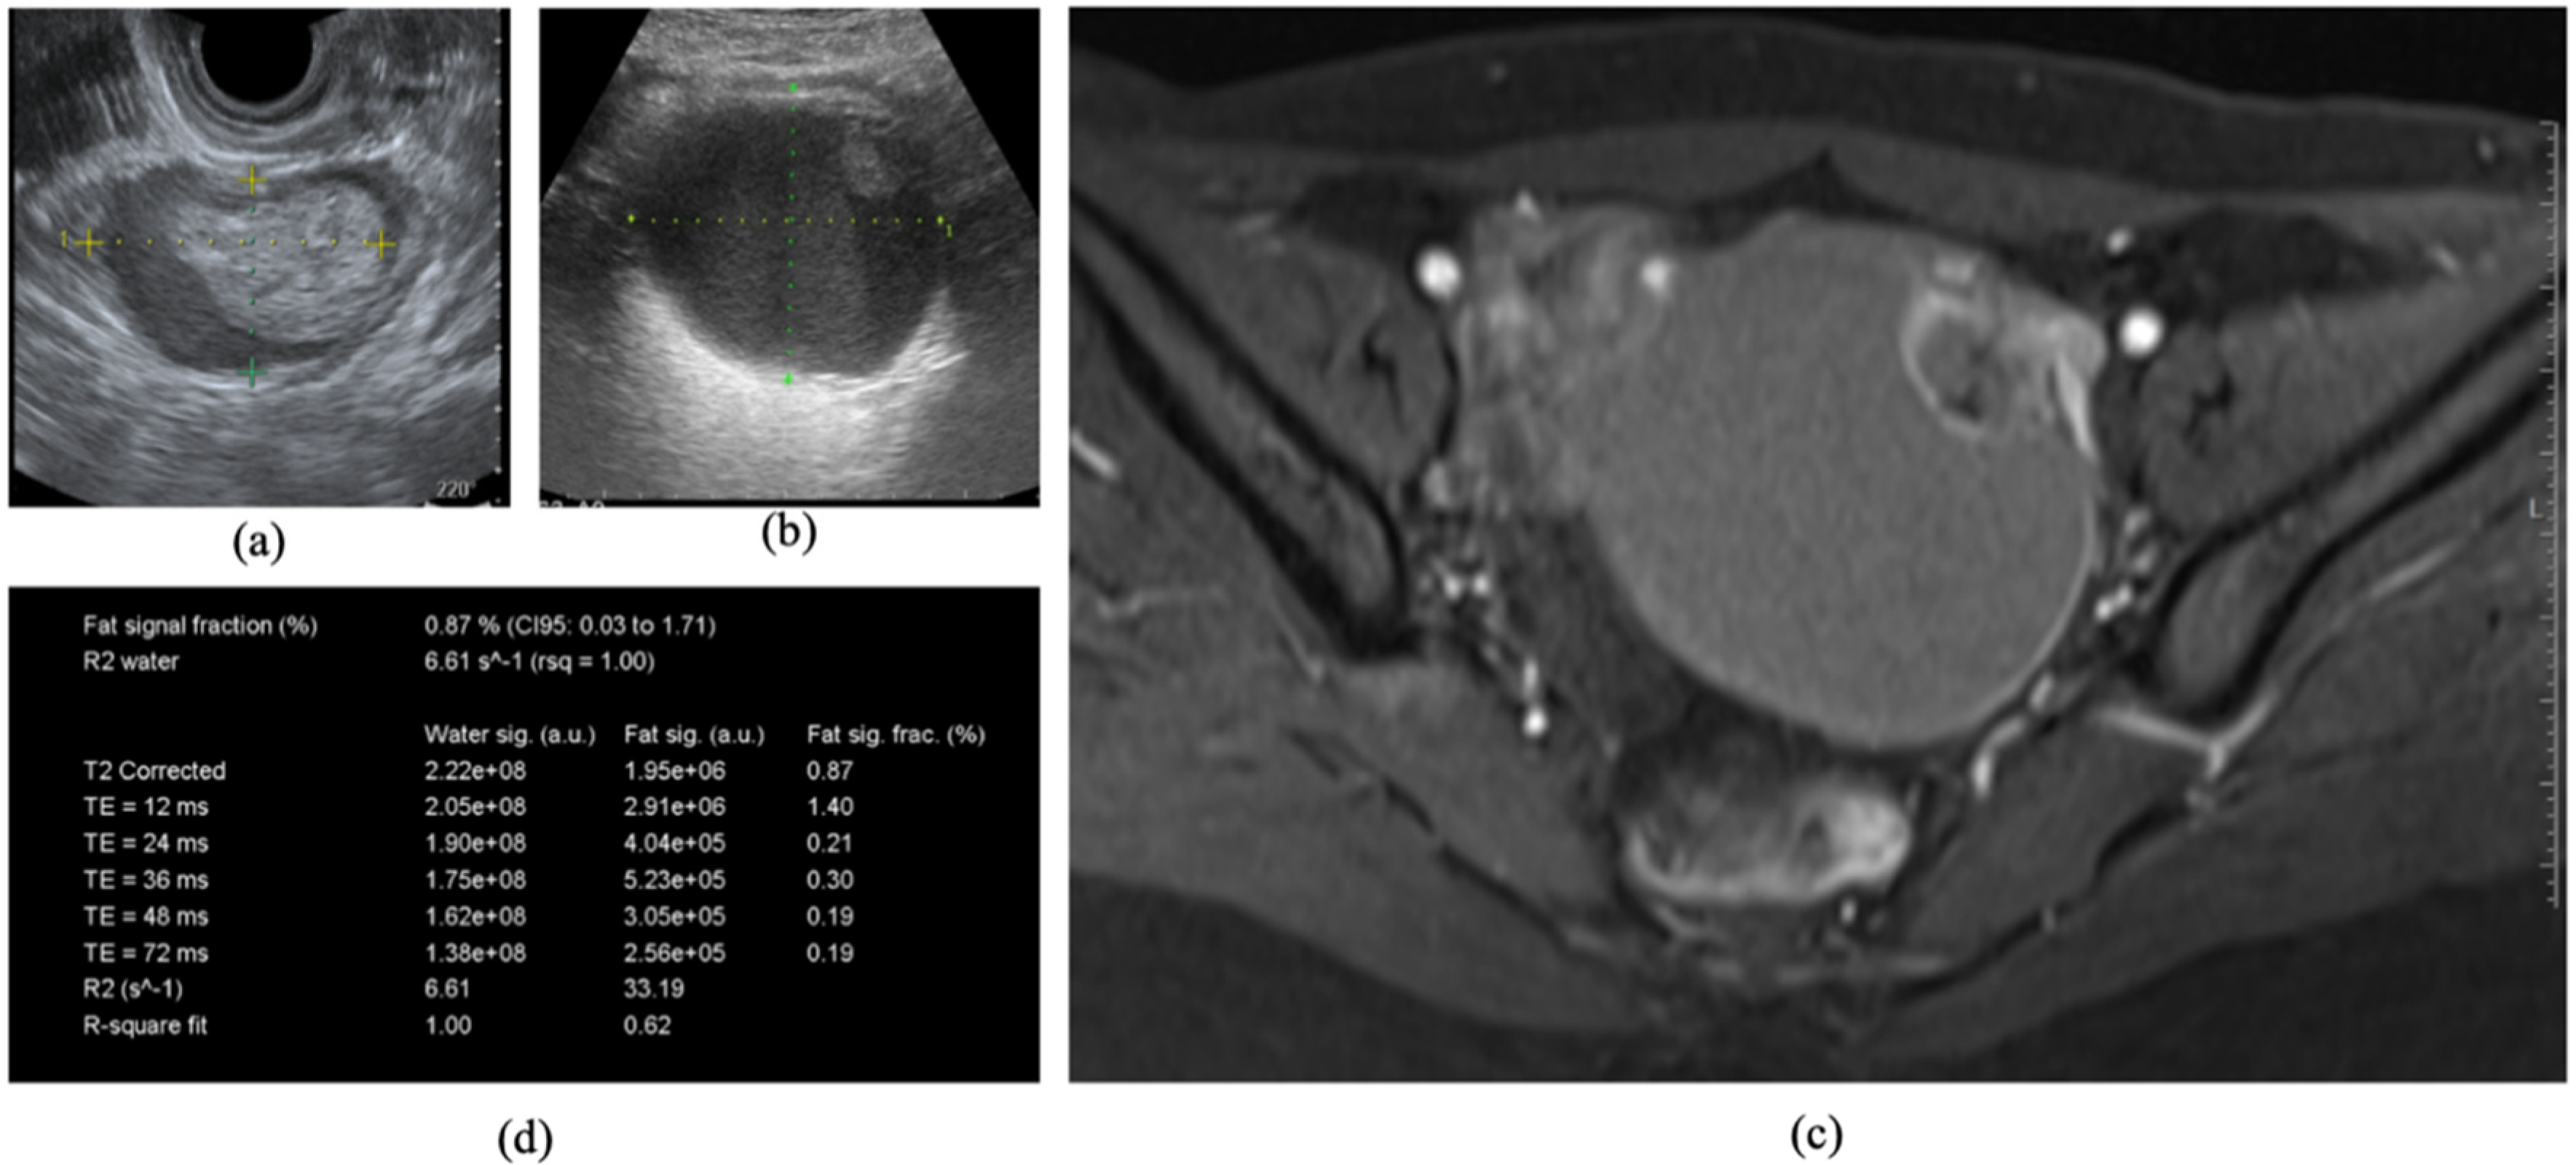

4. Case Report

A 31-year-old primigravida Japanese female was referred to our outpatient clinic with left side ovarian endometrioma (47 × 31 mm). She had no history of gynecological diseases such as endometriosis, abdominal pain, or abdominal surgery. On physical exam, external genitalia, vagina, and cervix were unremarkable; however, a pelvic exam revealed a non-tender mass in the left adnexal region. Figure 2a shows a characteristic sonographic finding with a clinically suspicious ovarian tumor. The CA125, CA19-9, and CEA assays were 44 U/mL, 24 U/mL, and 0.9 ng/mL, respectively. The R2 predictive index (22.38) suggested benign ovarian endometrioma. She presented to our hospital for every 3-month follow-up of the left endometrioma. Two years after the first administration, ultrasonography showed an enlarged ovarian cystic tumor (96 × 79 mm) with a solid portion (Figure 2b), which was indistinguishable from a solid part or clot. The levels of CA125, CA19-9, and CEA were 30 U/mL, 14 U/mL, and 1.1 ng/mL, respectively, and the R2 predictive index (18.25) suggested a malignant transformation. An MRI identified the solid tissue components, detected with enhancing on dynamic contrast-enhanced images (Figure 2c). The patient was evaluated by a gynecologic oncologist and radiologist. The patient was advised to have an MR relaxometry of the pelvis. After obtaining informed consent for conducting an MR relaxometry, an R2 value showed as 6.61 s-1 in the cyst (Figure 2d), which suggested a malignant tumor rather than benign ovarian endometrioma. She finally underwent surgical treatment including hysterectomy, adnexectomy, omentectomy, retroperitoneal, and para-aortic lymphadenectomy. The final histopathological results revealed endometrioid carcinoma within an endometrioma, International Federation of Gynecology and Obstetrics stage IA. Peritoneal washings were negative for malignant cells.

Figure 2.

The patient underwent a routine ultrasound and MRI using T1W and T2W sequences. An MRI examination of the pelvis on a 3.0-Tesla MR unit (MAGNETOM Verio, Siemens Healthcare, Erlangen, Germany), using a pelvic-phased array coil followed. The mural nodules were demonstrated as polypoid structures. A cystic mass with hematoma (47 × 31 mm) was observed by ultrasound (a), but two years after the first administration, ultrasonography showed an enlarged ovarian cystic tumor (96 × 79 mm) with an solid portion (b). MRI identified the solid tissue components, detected with enhancing on dynamic contrast-enhanced images (c), and MR relaxometry demonstrated an R2 value of 6.61 s-1 in the cyst (d).